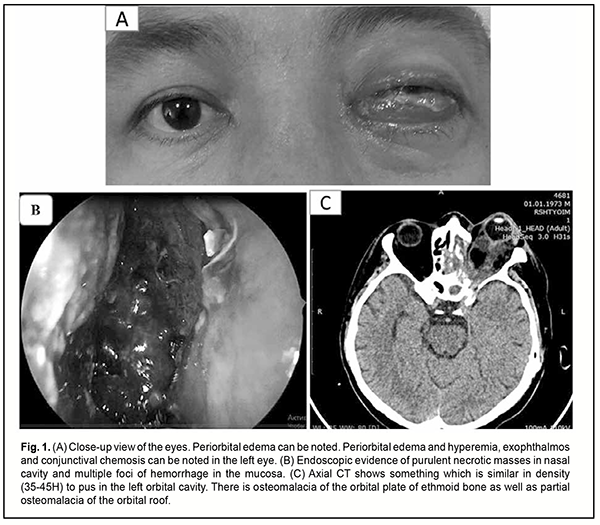

Introduction It has been demonstrated that patients with a severe course of COVID-19 tend to develop thromboembolic complications [1, 2]. Cavernous sinus thrombosis (CST) is one of the most dangerous disorders of the venous system of the brain with involvement of the visual pathway. The disease is usually caused by infection of the oral and nasal cavities, maxillary and frontal sinuses, and facial soft tissue, as well as by septic processes in a body weakened by chronic disorders [3, 4, 5]. In the Republic of Uzbekistan, the rate of CST among former COVID-19 patients has unprecedentedly increased, with almost 300 such cases registered by November 2020 [6]. Hereby we report a case of severe CST associated with COVID-19. Case report A male patient presented to the Multifield Clinic of Tashkent Medical Academy with complaints of severe pain in the left face, loss of sight, purulent nasal discharge, shortness of breath, cough, and weakness. His history was significant for years of type 2 diabetes mellitus. In addition, the patient received treatment for COVID-19 in July, 2020. Ten days after discharge from the in-patient setting, he started noting swollen eyelids, blepharoptosis and vision loss in the left eye, severe headache and nausea, and was hospitalized for these symptoms. The patient reported that he gradually started noting blepharoptosis and vision loss in the left eye after he initially experienced shortness of breath through the nose. Subsequently, these symptoms were accompanied by severe headache. The patient was diagnosed with meningoencephalitis of the frontal lobes. As he had a history of COVID-19, exhibited frontal lobe abscesses, hemorrhage into a right frontal lobe abscess cavity, and retrobulbar abscess, and had pansinusitis, cavernous sinus thrombosis, type 2 diabetes mellitus, and left interstitial pneumonia, he underwent “emptying and draining frontal lobe abscesses through trephine openings made one on each side of the head under local anesthesia”. Following this procedure, the patient experienced some improvement, with clarified consciousness and a reduction in body temperature. After he was consulted by neurosurgery, it was decided to continue his treatment under the supervision of maxillofacial surgeons and ophthalmologists. On examination, his general condition was bad, body temperature was 37.8 °C, skin and mucous membranes were pale; the respiration was vesicular; no rales; respiration rate, 24/min; blood pressure, 120/80 mmHg; and heart rate, 89/min. The peripheral lymph nodes were enlarged. Left eye examination findings were as follows: pattern vision with left amaurosis; a swollen and hyperemic periorbital area; ophthalmoplegia; exophthalmos; conjunctival chemosis; transparent cornea; decreased corneal sensation; moderately deep anterior chamber; transparent aqueous humor; widened pupil; absence of pupil light reflex; and partial lens opacity. Detailed ophthalmoscopy was not possible (Fig. 1).

Figure 1 (B) shows a CT image of the patient. Axial CT shows something which is similar in density (35-45H) to pus in the left orbital cavity. There was osteomalacia of the orbital plate of ethmoid bone as well as partial osteomalacia of the orbital roof. In addition, purulent material in the maxillary sinus cavity and signs of frontal lobe encephalitis were seen. Laboratory test results included: C-reactive protein, 80 mg/L; Antistreptolysin O, 300 ul/ml; antineutrophil antibodies, 0.10; D-dimer, 1206 ng/ml; fibrinogen, 743 mg/dl; activated partial thromboplastin time, 32 sec; prothrombin index, 87%; prothrombin time, 16 sec; and international normalized ratio (in the presence of anticoagulation therapy), 1.35. The diagnosis was established based on the results of clinical and laboratory tests and imaging studies Major diagnosis: Cavernous sinus thrombosis and left chronic purulent pansinusitis in the acute phase. Complication: abscess in the orbital cavity. Concomitant diagnosis: Post-COVID-19 condition. Left interstitial pneumonia condition. Post-frontal lobe abscess drainage condition. Type 2 diabetes mellitus. An expert panel of related specialties decided that a functional endoscopic sinus surgery (FESS) with debridement and decompression of the orbit had to be conducted by a team of ophthalmologists, maxillofacial surgeons and otolaryngologists. Approximately 15-20 milliliters of purulent material were evacuated from the orbital cavity. Revision of the cavity confirmed purulent-and-necrotic melting of the orbital plate of ethmoid bone as well as a portion of the orbital roof. Subsequently, ethmoidotomy and maxillary sinusotomy and evacuation and drainage of purulent material were conducted. Postoperatively, the patient improved progressively in the presence of lavage of the cavities with antiseptic solutions and comprehensive systemic medical therapy. At day 5 after surgery, eye swelling improved, but amaurosis, and ophthalmoplegia were still present, and periorbital skin sensation was still absent. In addition, ophthalmoscopy showed diffused retinal and optic disc edema. Discussion The reviewed case of cavernous sinus thrombosis had an untypical clinical course. Cavernous sinus thrombosis cannot be clearly classified as aseptic or septic with regard to characteristics of changes and time points of changes in pathognomonic signs. On the one hand, there was a gradual increase in symptoms, which is characteristic for an aseptic course and was confirmed by coagulation tests. On the other hand, orbititomy demonstrated signs of orbital phlegmon, which result in the development of septic cavernous sinus thrombosis. It is, however, difficult to determine whether the development of unilateral purulent pansinusitis with involvement of the orbit preceded cavernous sinus thrombosis with a subsequent purulent-and-necrotic process in the sinuses or the latter preceded the former. The D-dimer level was five times higher than normal in our patient who had been taking platelet antiaggregants and indirect anticoagulants for years. This finding indicates that he could develop COVID-19-associated coagulopathy, likely a major factor leading to the above condition. In addition, of note that C-reactive protein and antistreptolysin O levels were substantially (13 times and 1.5 times, respectively) higher than normal; this may indicate that the patient had vasculitis. Conclusion We may conclude that we encountered an unusual course of cavernous sinus thrombosis which does not conform to the general regularities of the course of this pathologic condition. It is noteworthy that more than ten similar COVID-19-associated cases have been registered in the Republic of Uzbekistan during the recent five months. Therefore, further and more systemic research work on this issue is required to elucidate the role of COVID-19-associated coagulopathy and vasculitis in the development of thrombotic and purulent-and-necrotic processes in the maxillofacial area.